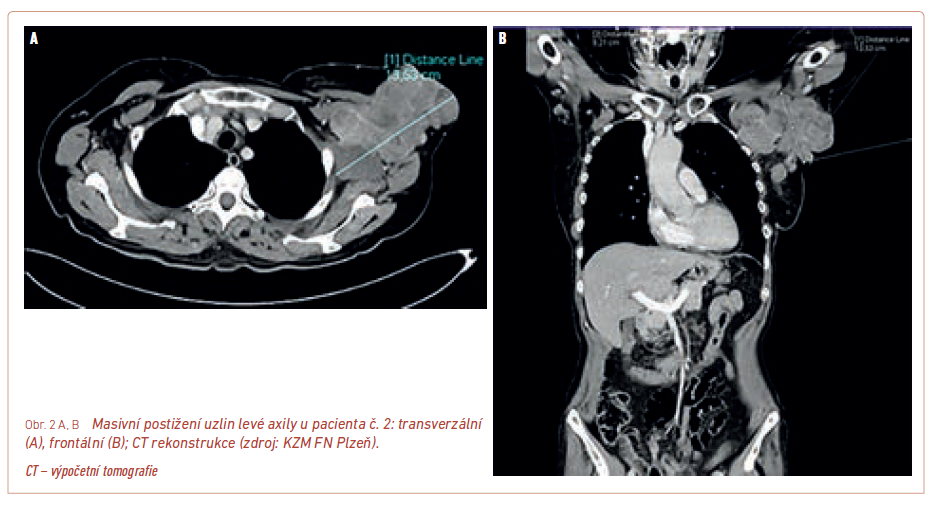

S ohledem na schopnost nádoru poměrně časně diseminovat je však zejména u pokročilejších lézí nutno doplnit další vyšetření, která pomohou určit stadium onemocnění. Nemocní by měli mít doplněno alespoň rentgenové (RTG) vyšetření plic a sonografické (SONO) vyšetření spádových uzlin a epigastria. Jelikož je dnešní léčba pokročilého a metastatického melanomu nákladná, jsou upřednostňována komplexnější a přesnější vyšetření – spíše výpočetní tomografie (CT) hrudníku a břicha nebo nejlépe vyšetření celotělovým PET/CT (pozitronová emisní tomografie/výpočetní tomografie) (obr. 1) umožňující posoudit i nález ve skeletu a mozku, který by měl být před zahájením terapie rovněž vyšetřen, aby byla možná úhrada léčby ze zdravotního pojištění. Navíc je CT nález přesnější a přehlednější, než jaký umožní běžné SONO vyšetření (obr. 2).